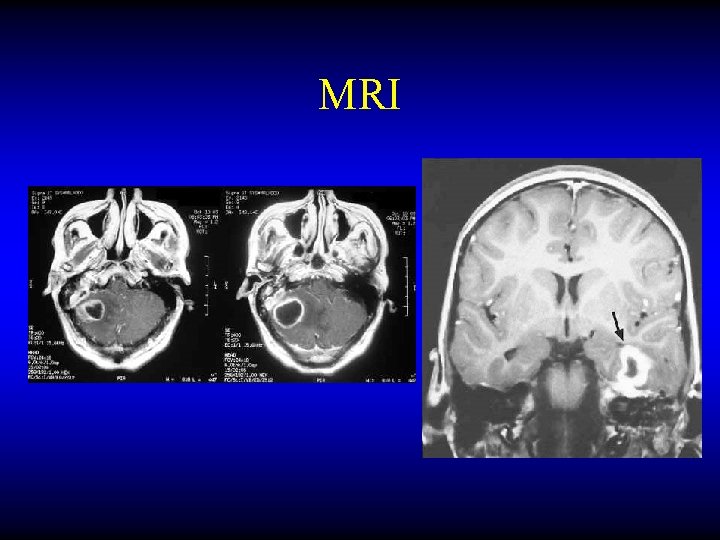

Otogenic brain abscess Diagnosis • CT • MRI

MRI